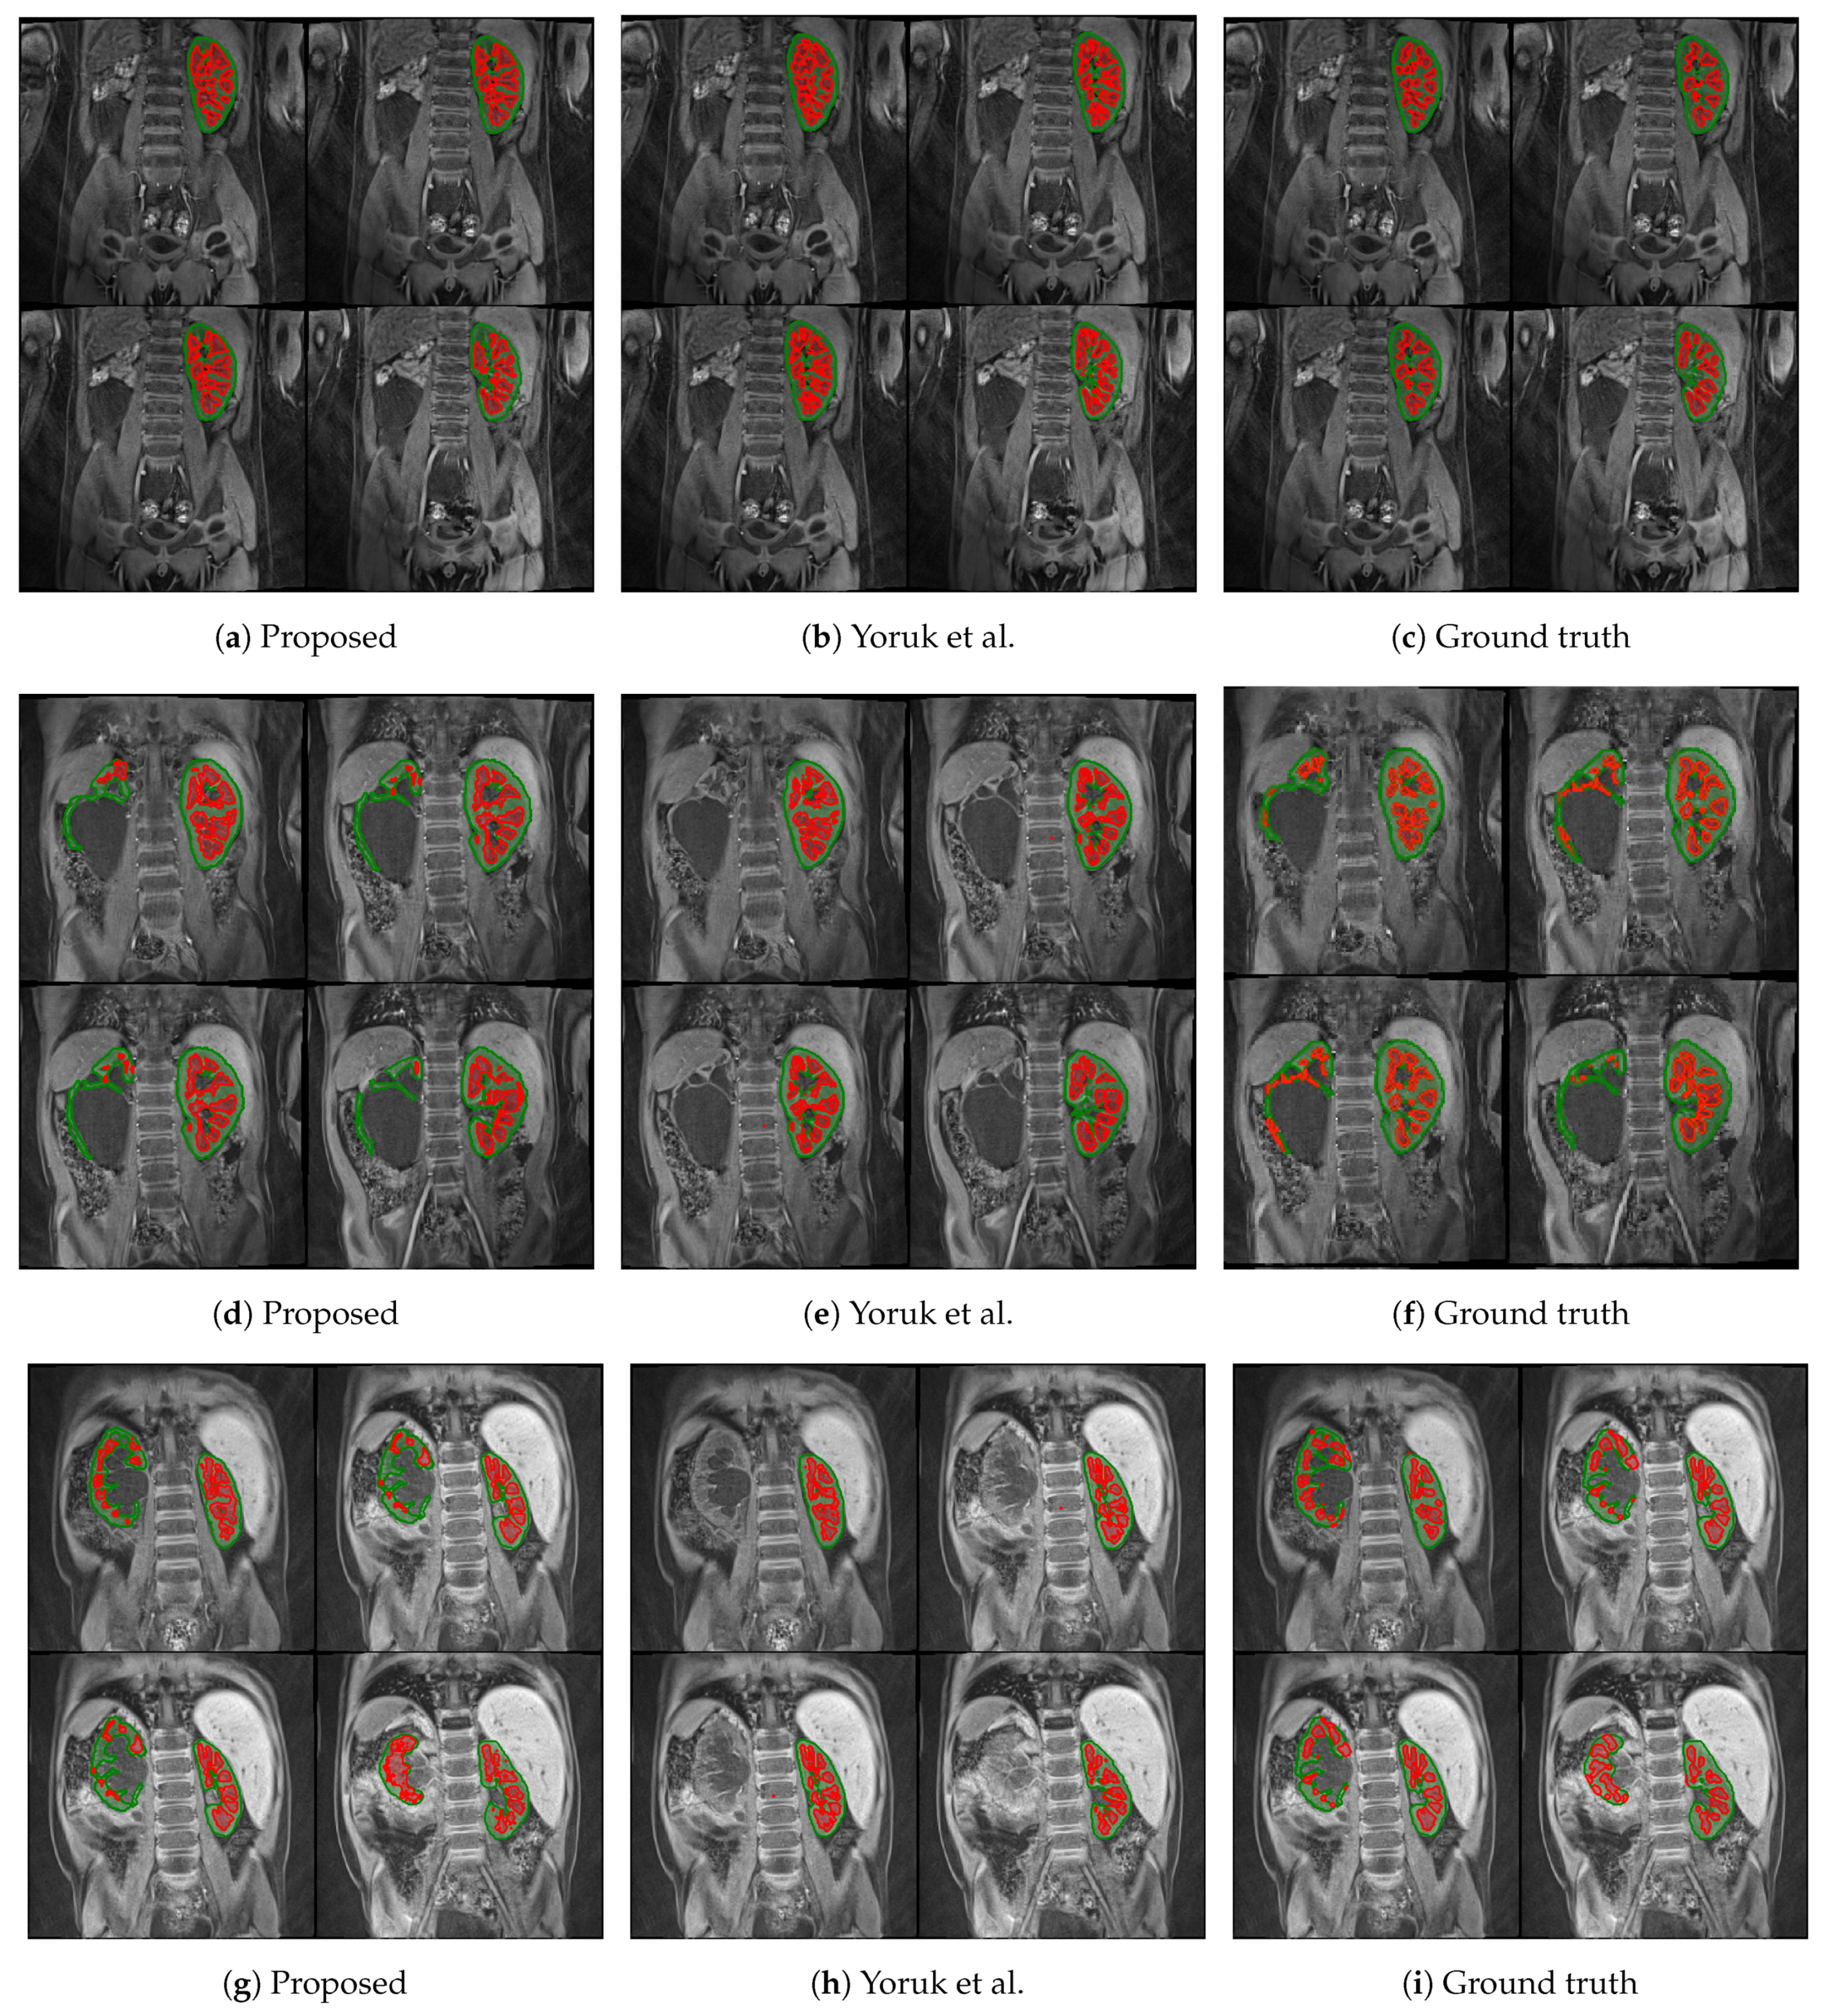

The first columns of Figure 5 and Figure 6 display the medulla (red) and cortex (green) segmentation results in four coronal slices from a single DCE-MRI scan depicting clinically “normal” and “abnormal” kidneys, respectively. Using contrast enhancement via gamma correction and sigmoidal transformation maintained the contextual information while differentiating kidney regions; this occurred mainly in temporal instances where the contrast between DCE-MR imaged renal compartments was low but enough to capture boundary differences where the medulla and cortex edges were in contact.

Figure 6.

Medulla and cortex segmentation results of three different clinically “abnormal” kidneys. The first column (a,d,g) shows the results from the proposed approach; the second column (b,e,h) shows the respective results using the baseline approach from Yoruk et al. [16]; the third column (c,f,i) shows the respective ground truth.

The proposed renal segmentation approach outperforms a baseline method [16] for extracting the medulla and cortex by approximately 9.3% and 17.1% in mean DSC, respectively, and it boasts higher statistical stability by approximately 15.7% and 12.4%, as shown in Table 3. An available implementation [34] is utilised to reproduce the baseline method. Whereas the baseline method utilises computer vision to extract the whole kidney, the approach proposed in this report employs advancing deep learning to predict highly diverse kidney features, especially of abnormalities. As shown in Figure 6e,h, the algorithm in [16] fails to detect one of the clinically “abnormal” kidneys, whereas the proposed approach has accurately identified the entire organ, as illustrated in Figure 6d and Figure 6g, respectively. Moreover, the baseline approach completely breaks down in a clinically “normal” case, as shown in Figure 5e. In contrast, the robustness of the deep-learning-based model captures both kidneys before renal segmentation is performed, as shown in Figure 5d. A limitation of this particular case (Figure 5d) includes a relatively higher false-negative cortex prediction, resulting in a higher false-positive medulla compared to the ground truth in Figure 5f. Therefore, thresholding parameters would require optimisation to ensure a more robust generalisability. Thus, it would be helpful to expand upon nature-inspired algorithms such as the firefly and swarm intelligence algorithms to determine multilevel thresholds and enhance the compartment segmentation efficiency. In Figure 5h, the binary dilation and erosion strategy in the baseline approach predicts false-positive labels of renal parenchyma, whereas the proposed trained deep learning model accurately localises the kidney. Furthermore, the relatively high concentration of false-negative medulla labels demonstrates the limitations of incorporating the GrabCut and SVM classifier, as in [16]. In comparison, the proposed renal segmentation method exploits intensity enhancement throughout the full temporal dimension of the DCE-MRI to generate the “optimum” medulla labels for the resultant segmentation, as highlighted in Figure 5g.